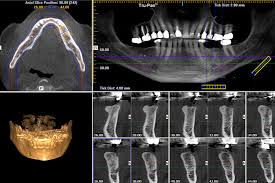

Cone Beam Computed Tomography (CBCT) is variation on conventional Computed Tomography (CT).